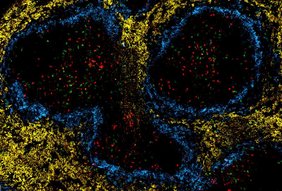

Laut Martin Väth ist das besonders wichtig, weil sich Nährstoffgehalt, Sauerstoffsättigung und andere metabolische „Stressfaktoren“ in Tumoren teilweise erheblich von gesundem Gewebe unterscheiden und weil T-Zellen aktiv auf diese Umgebung reagieren müssen. Neue technische Entwicklungen, wie räumliche Transkriptom- und Metabolom-Analysen, bieten erstmals die Möglichkeit, diese Fragen systematisch und hochauflösend im Gewebeumfeld zu untersuchen.